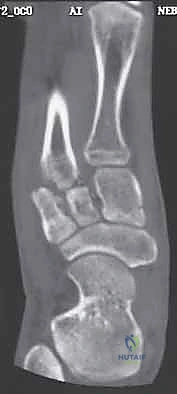

3. التصوير المقطعي المحوسب (CT Scan)

في الحالات المعقدة، أو عند التخطيط للجراحة، يُعد التصوير المقطعي أداة لا غنى عنها. فهو يوفر صوراً ثلاثية الأبعاد تفصيلية للعظام، مما يسمح باكتشاف الكسور الدقيقة جداً (Micro-fractures) وتقييم مدى الإزاحة في المفاصل، وهو أمر حيوي لنجاح أي تدخل جراحي.